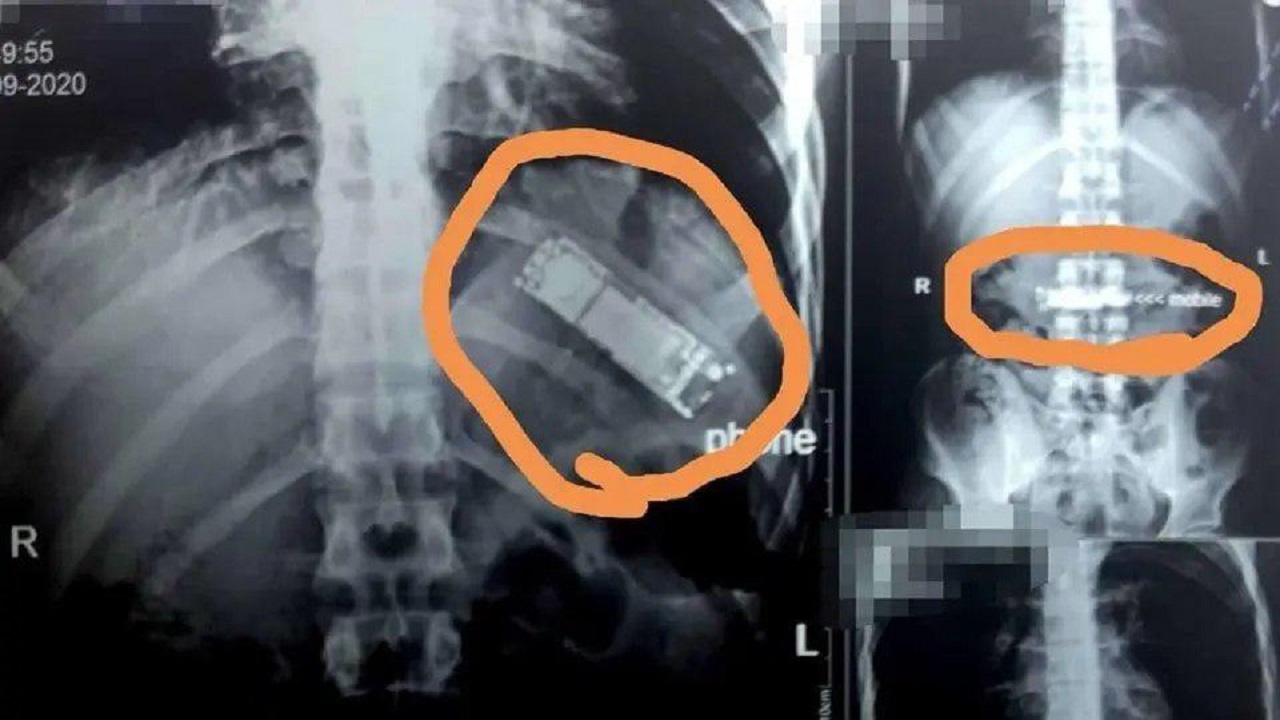

تیم پزشکی بر همین اساس تصمیم گرفت از معده او عکسبرداری کند و نتایج این عکسها حیرتآور بود. آنها جسم مشکوکی در معده او یافتند که مشخص شد یک دستگاه تلفن همراه است.